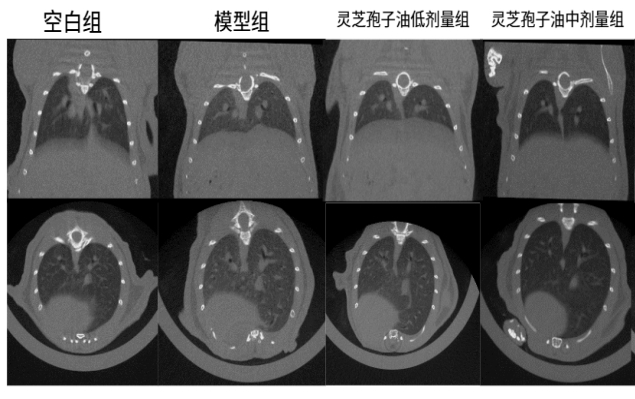

体内功效实验研究结果表明:在为期52天的小鼠实验中,每日6粒广药牌灵芝孢子油,灵芝孢子油显著减少了肺部肉芽肿结节的面积(减少23.07%)和磨玻璃阴影,降低炎症因子和趋化因子水平 ,证实广药牌灵芝孢子油具有一定的防治小鼠肉芽肿型肺结节的作用。

图:灵芝孢子油对肉芽肿型肺结节小鼠肺部断层扫描检测结果及统计

体内作用机制研究证实:通过调节PI3K-Akt-mTOR信号通路、抑制p-AKT和p-mTOR活化、纠正代谢紊乱、减少炎症因子和趋化因子的释放,最终达到缓解肉芽肿型肺结节的效果。